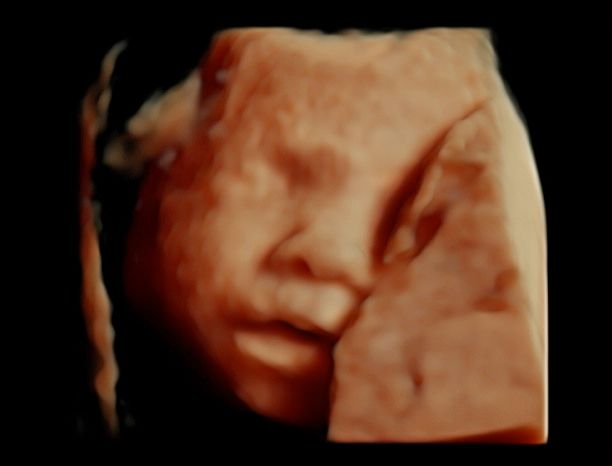

Foto e video